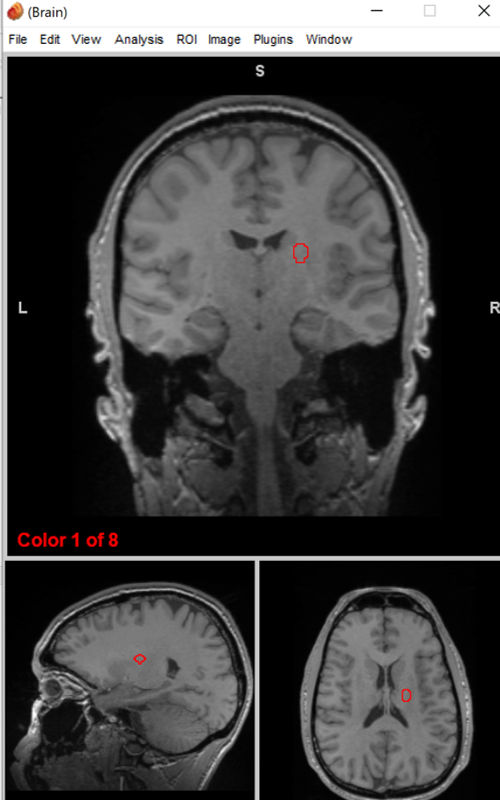

putamen/globus pallidus

regulate voluntary movement, motor planning, and learning